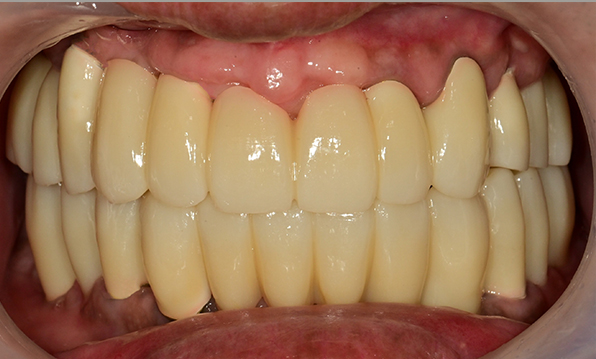

Before & After

| Before | After |